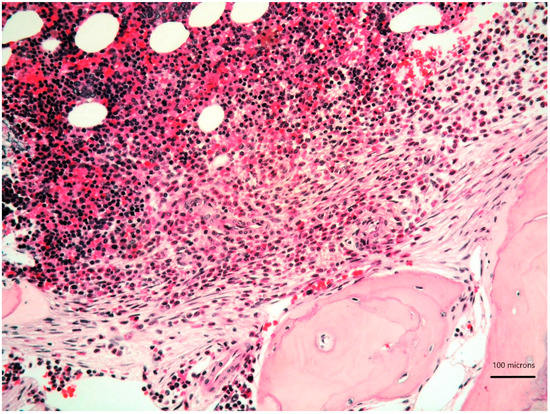

A 79-year-old woman was referred for a long history of peripheral eosinophilia. She underwent right hemicolectomy for colonic polyposis a few years before. Laboratory tests disclosed mild macrocitic anaemia (Hb 10.4 g/dL, MCV 93%) and eosinophilia (leukocytes 3360/mmc, eosinophils 30%). β2 microglobulin (3256 ng/dL; reference range 1010–1730) and serum tryptase (138 ng/L; reference range 0–11.4) were elevated. Serum immunofixation revealed IgA/kappa monoclonal protein (21 g/L). Bence-Jones protein was positive. Bone marrow (BM) biopsy revealed two neoplastic components. Low- and high-power views of haematoxylin and eosin sections showed cohesive paratrabecular aggregates of bland-looking, spindle-shaped cells (Figure 1; Figure 2 lower part) positive for CD117 (Figure 3), tryptase and CD25 representing 20% of marrow cellularity. Aggregates of mature plasma cells (Figure 1; Figure 2 upper part) positive for CD138 (Figure 4), MUM1/IRF4 and kappa light chain occupied 40% of the remaining bone marrow. Bone marrow aspirate confirmed the presence of the two neoplastic components (Figure 5). KITD816V mutation was detected by DHPLC and confirmed by Sanger sequencing; TET2 mutation was identified using DNA sequence analysis on marrow aspirate. Monoallelic deletion of TP53/17p13 and trisomy of ATM/11q23 was detected by FISH analysis on BM enriched with plasma cells using CD138+ magnetic Micro-Beads, respectively, in 39% and 94% of nuclei. RUNX1, ASXL1, SRSF2 and U2AF1 were unmutated. Osteoporosis was identified by full skeletal X-rays and MRI. The case was referred to as SM with concomitant smoldering MM.

Figure 1. Bone marrow biopsy showing paratrabecular aggregates of spindle-shaped cells (lower part) close to clusters of mature plasma cells (upper part) (haematoxylin and eosin, 200× magnification).

Figure 2. High-power view of bone marrow biopsy highlighting morphological details of bland-looking spindle cells (lower part) and mature plasma cells (upper part) (haematoxylin and eosin, 400× magnification).